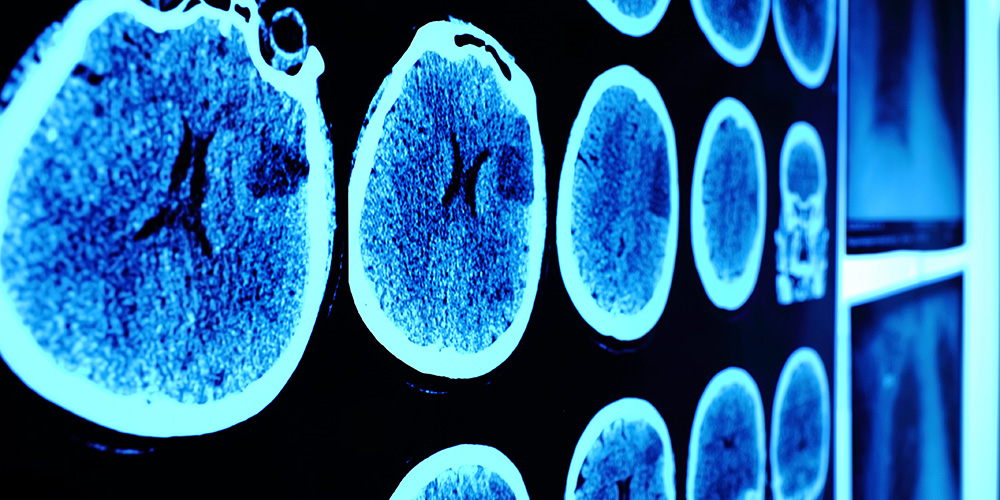

The Shideng Bao lab studies glioma stem cell signaling pathways in malignant brain tumors, including glioblastoma.

Dr. Peiwen Chen’s lab studies biological and molecular processes related to primary and metastatic brain cancers.

The Jeongwu Lee lab studies glioblastoma, focusing on cancer progression and treatment resistance.

The Jennifer Yu lab studies glioblastoma and mechanisms underlying stem cell maintenance and therapeutic resistance.